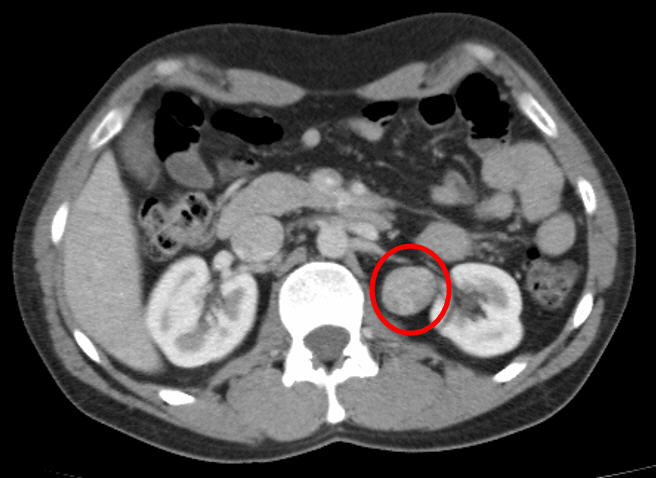

I saw a Haematologist for approx. 2 months in which I had blood tests etc and while I had low platelet count (Thrombocytopenia) it was not medically something to worry about and in fact medical records showed that I had a low count back in 1999 and infections/fevers will cause a drop in white cells. However my symptoms – fatigue, nausea, shortness of breath, loss of appetite had him a little concerned then as by pure accident I did mention that I get stomach cramps all the time and on examination it was a little painful (6/10) where pressure was applied. A full Abdominal CT scan was booked just to make sure.

It was the end of March (31) when I had my CT Scan and on April the 1st I received the call – there is a lesion on your Kidney and I have booked you in for an Intravenous Ultra Sound in 2 days. Questions! Well I didn’t know what to say.. What did it mean? What was an intravenous ultra sound?

I really didn’t have to wait long, I was at my last Haematologist appointment where I was advised that I have “Key Characteristics” that warrant treatment for a malignant Kidney Cancer at the age of 37. My next appointment was in the care of Urology where it was again indicated that I have Kidney Cancer and treatment options were planned but nothing was conclusive during this time. Out of the blue in June’14 I received a phone call from my treating urologist and was advised that I would be booked in for a Biopsy, this rattled me emotionally as the plan had changed and I wasn’t convinced. You see my tumour is not in the kidney but it is on the Renal Artery – “not your classic kidney cancer” I was informed.

Biopsy Results – it has now been confirmed that I have Renal Chromophobe Carcinoma (a rare type of Kidney Cancer). The tumour is approx. 4cm in size sitting on the left renal artery and the plan is to remove the tumour, part of the artery and 1/3 of the kidney. Like all surgery it has its risks but mine has its own set of rules – I will be more than likely to be having open chest surgery as the location of the tumour is higher than normal and it is very close to the Aorta and right next to the spleen. There is also the possibility that a full removal of the left kidney may occur as the scans aren’t clearly showing if the tumour is touch both sides of the kidney. Surgery will occur on the 4/07/2014.In conclusion I guess I don’t meet the statistical guides of kidney cancer, never really had typical symptoms and due to a really thorough Haematologist I am lucky to have it diagnosed this early. I didn’t feel the need to google around on the web as I requested a Kidney Cancer pack which got sent out to me as well as the website both of which gave me plenty of information about Kidney Cancer and what to expect. I do however find myself a little isolated given the end diagnosis and very little information about this particular cell mutation and what are the statistics for this. I was never really overweight (obese), don’t drink alcohol (occasionally – 1 every 4 years), never smoked so I cant really see why I would have Kidney Cancer – but I do and what will be will be.